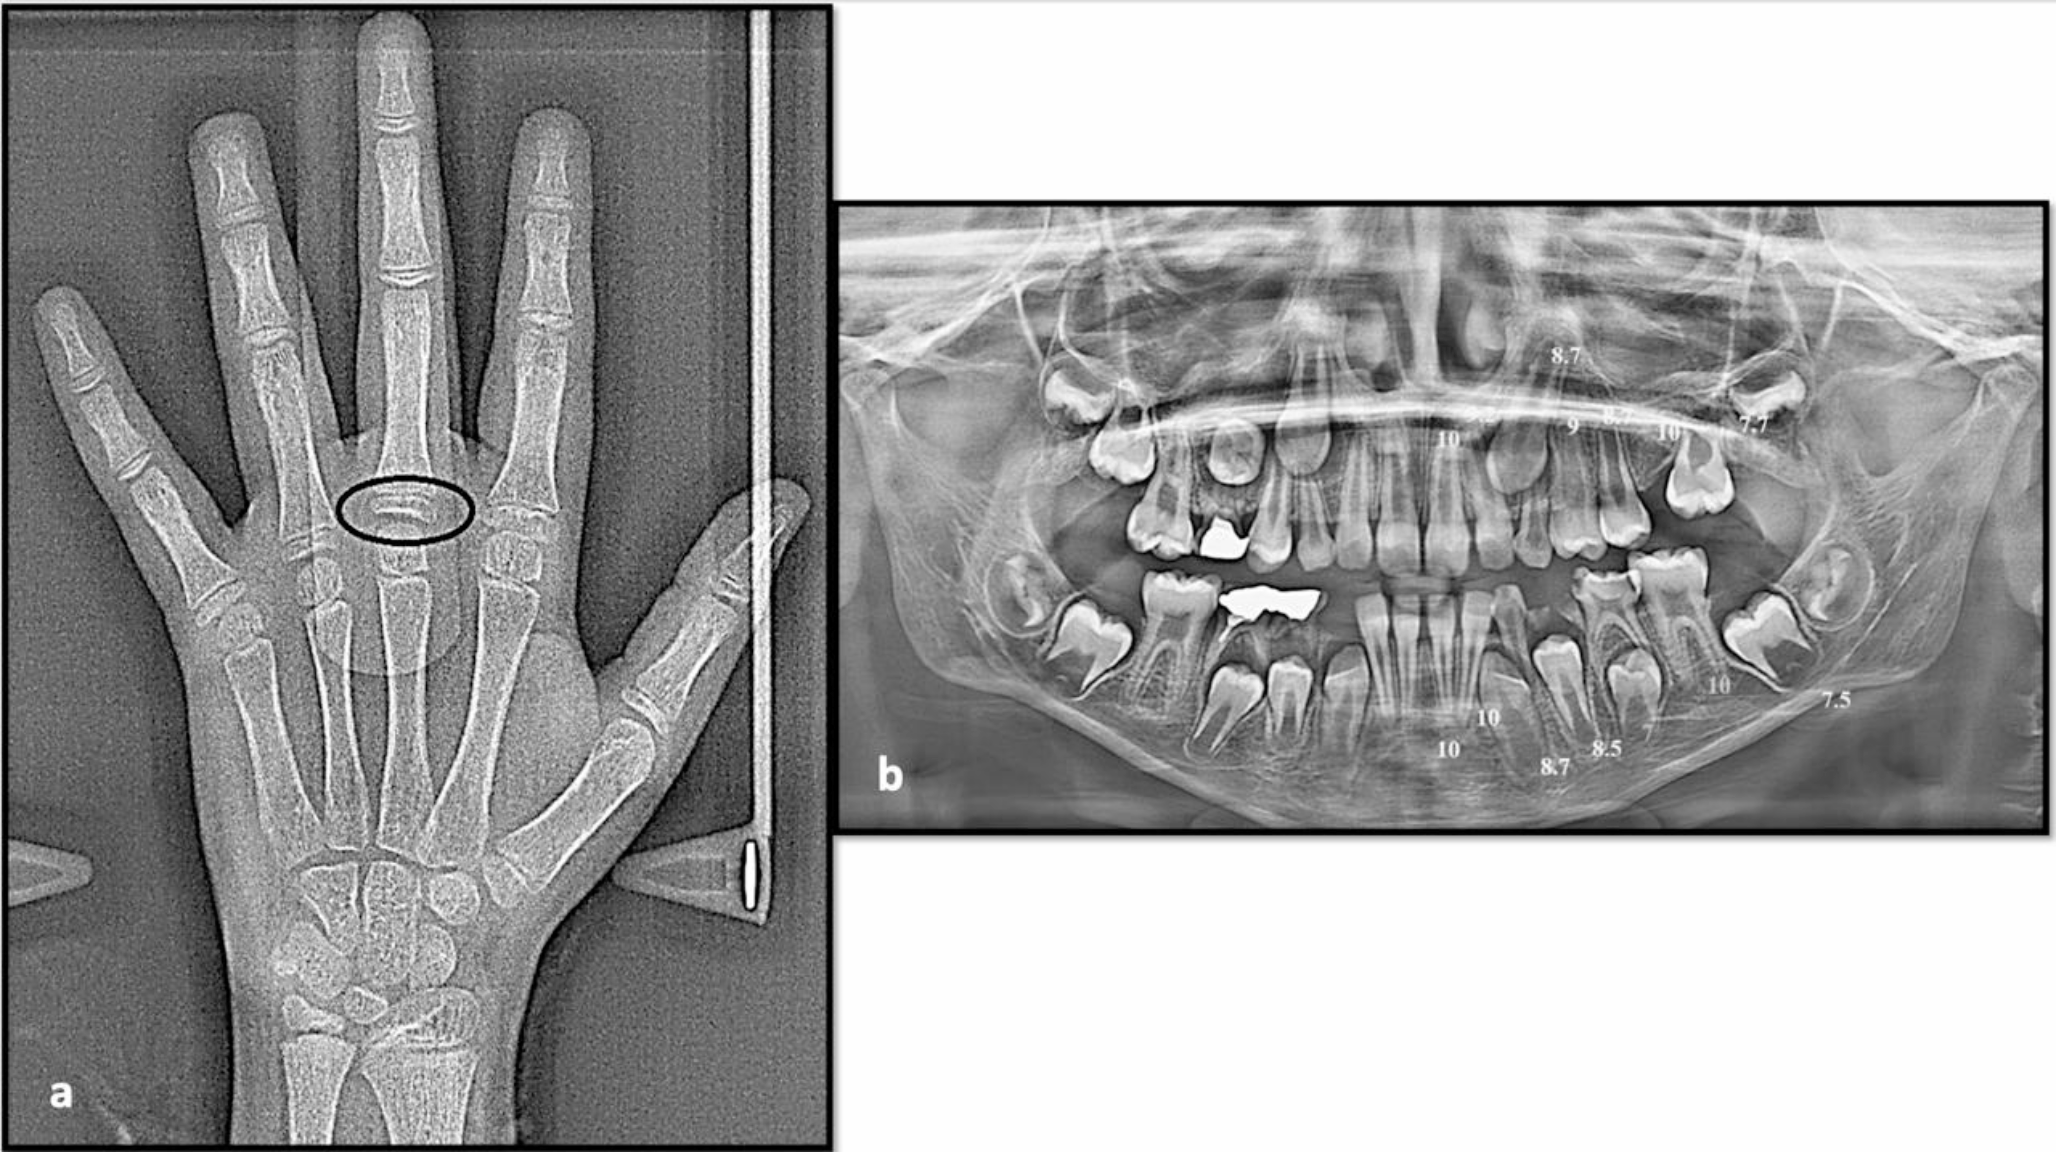

Fig. 2

a) Hand-wrist X-ray of a 9.05-year female patient showing different sites (in black) of skeletal maturity indicators (SMI) assessed by Fishman method; the proximal phalanx of the third finger showed equal width of the epiphysis and diaphysis (SMI = 1), and skeletal age is 10.23 years, b) Panoramic X-ray of the same patient showing different scoring of dental development of the mandibular and maxillary teeth on the left side (except the third molar), marked according to the Nolla method; the total scoring was 118 and the calculated dental age was 9 years

Bild vergrößern